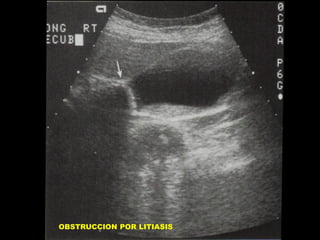

SOBREDISTENSION DE LA

VESICULA BILIAR

• AYUNO PROLONGADO

• OBSTRUCCION DE LA VESICULA

O DEL ARBOL BILIAR.

• VESICULA BILIAR NORMAL

OBSTRUCCION POR LITIASIS